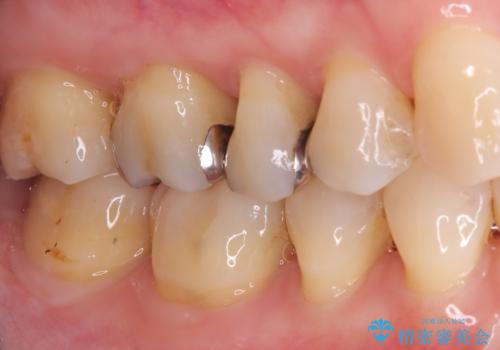

治療では、まず古い金属のインレーを慎重に取り外しました。金属の下に隠れていた虫歯の再発がないかを確認し、歯を丁寧に形成。その後、精密な型取りから患者様の歯の色に合わせたオーダーメイドのセラミックインレーを作製しました。セラミックは、自然な光の透過性を持つため、周囲の歯と区別がつかないほどの美しい仕上がりとなります。適合性の高いセラミックインレーを装着することで、再発のリスクを抑えつつ、長年のコンプレックスだった銀歯がなくなり、笑顔でも気にならない自然な奥歯を取り戻していただけました。